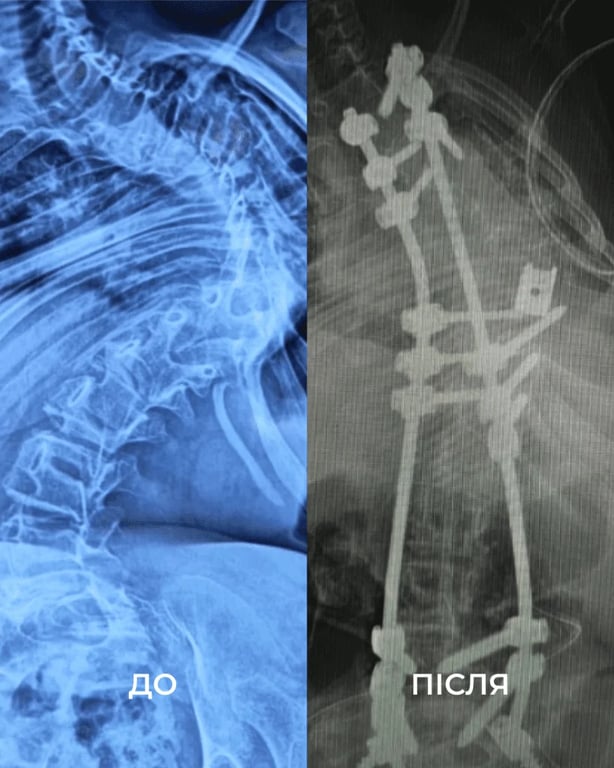

хребет

Позвоночник ребенка до и после операции. Фото: Первое медицинское объединение Львова

После двух операций, 18 часов наркоза и из-за слишком слабых мышц две последующие недели девочка пробыла в реанимации под кислородом. Но хирургам удалось выровнять позвоночник девочки на 85%.